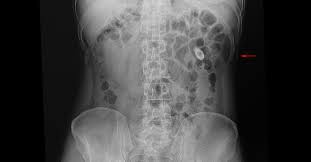

The strong odor is often compared to ammonia, but it's more likely that the smell stems from a urinary tract infection than a kidney stone. Kidney pain location and sensation. 3 stone fragments that were removed during percutaneous surgery. Smaller the size of a stone, the faster it can pass through the urinary tract. It may also be a dull ache depending on the diagnosis. A kidney stone forms in the body as a result of the lack of liquid in the urine. Stone composition (or type) is indicated when available. Stones in the gallbladder gallstones gall stones gall bladder stones healthcare for kidney cholecystitis biliary gallbladder man kidney pain woman kidney pain. خانه > pic > show me pictures of kidney stones. Ever wondered how big a 4mm kidney stone was? As the condition is common, you may wonder about the risk factors. X ray photos of kidney stones. A stone 5mm in size or smaller should pass, albeit with some degree of pain and with drinking lots of water.

Kidney stones range in size from just a speck to as large as a ping pong ball. Pain associated with kidney stones is often felt in the abdomen, groin, or the flank area. About 5% of people develop a kidney. In some cases of kidney pain, there are a few simple steps to alleviate the pain in your back. We've gathered a collection of kidney stone pictures in this photo gallery. A probe placed on the skin reflects sound waves off the kidneys, creating images on a screen. Kidney stones cause a distinct set of symptoms including severe flank pain, nausea, vomiting, and sometimes blood in the urine.kidney stones are diagnosed once the doctor has ruled out other potential causes of flank pain.imaging studies, such as ultrasound or a helical ct scan without contrast, may be performed to confirm the diagnosis. But this vid will give you a first hand look! Staghorn calcium oxalate kidney stone. For example, a 2mm stones may pass through the kidneys in about 12 days but stones of size 4mm can take about 30 days to pass out. Small stones may travel easily down the ureter and be expelled by the body in the urine. The stones include small passed stones up to large staghorn stones. X ray photos of kidney stones.